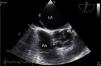

A 38-year-old female liver donor candidate was referred to our cardiology clinic for preoperative evaluation. The patient had no symptoms. On physical examination, a grade 2/6 early diastolic murmur was heard at the third left sternal intercostal space. Her blood pressure was 140/70 mmHg. Transthoracic echocardiography revealed moderate aortic regurgitation (AR) with the suspicion of quadricuspid aortic valve (QAV). Left ventricular end-diastolic and end-systolic diameters were 5.6 cm and 4.0 cm, respectively. Ejection fraction was normal. Transesophageal echocardiography confirmed the diagnosis of QAV with four equal cusps (Type A) (Figures 1 and 2, Video 1) with moderate AR (Figure 3). The patient was removed from the donor list with a suggestion for regular outpatient cardiology clinic visits.